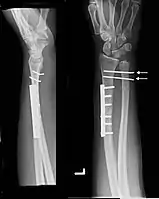

Images

Galeazzi fracture after surgical fixation